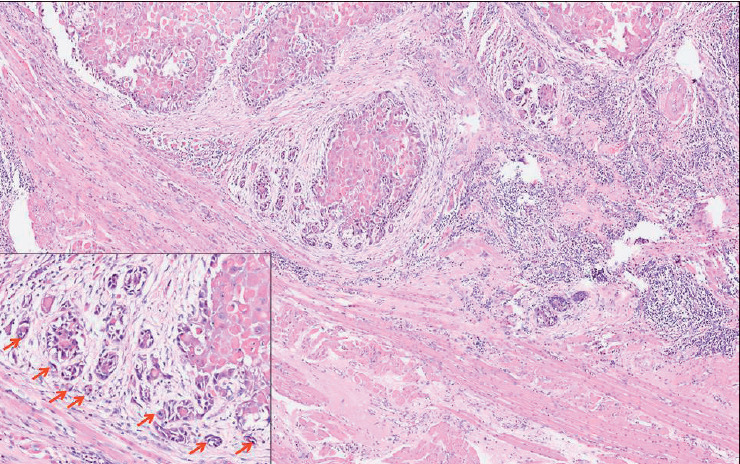

目的:口腔鳞状细胞癌是世界上最常见的头颈部恶性肿瘤。肿瘤出芽是一种组织病理学特征,其特征是在侵袭性肿瘤前部的基质中分散存在孤立的单个/小簇癌细胞。在印度,其在唇部和口腔鳞状细胞癌中的预后意义尚未得到太多研究。本研究的目的是在印度北喀拉拉邦的一个三级癌症中心对333例口腔鳞状细胞癌患者进行大型单中心回顾性队列研究,探讨肿瘤出芽在预后中的作用。材料与方法:从病理档案中检索2018 - 2020年333例口腔鳞状细胞癌的初切切片,由2名独立病理学家对肿瘤出芽及其他组织病理参数进行评估。生存数据从患者档案中收集。结果:我们使用卡方分析发现肿瘤出芽与其他已知的组织病理学预后因子之间存在显著关联。单因素logistic分析显示,肿瘤出芽、浸润深度(bbb10 mm)、最坏浸润方式5和神经周围浸润与局部复发/远处转移显著相关。多因素logistic回归分析发现肿瘤出芽是局部复发/远处转移的独立预后指标。单因素cox比例分析显示,口腔鳞状细胞癌患者的肿瘤出芽、浸润深度(bbb10 mm)、最坏浸润方式5、病理T4分期和神经周围浸润与总生存期降低和无病生存期差相关。多变量cox比例分析显示,肿瘤出芽是总生存期下降和无病生存期差的唯一独立预测因子。结论:基于本研究,我们可以得出结论,肿瘤出芽是一个简单可靠的独立预后指标,有助于口腔鳞状细胞癌患者的个性化治疗。

Objective: Oral squamous cell carcinoma is the most common head and neck malignancy reported worldwide. Tumor budding represents a histopathological feature characterized by the presence of isolated single/small clusters of cancer cells dispersed within the stroma at the invasive tumor front. Its prognostic significance has not been studied much in lip and oral squamous cell carcinomas in India. The aim of this study was to investigate the prognostic role of tumor budding in a large single-center retrospective cohort of 333 patients with oral squamous cell carcinoma at a tertiary cancer center in North Kerala, India.